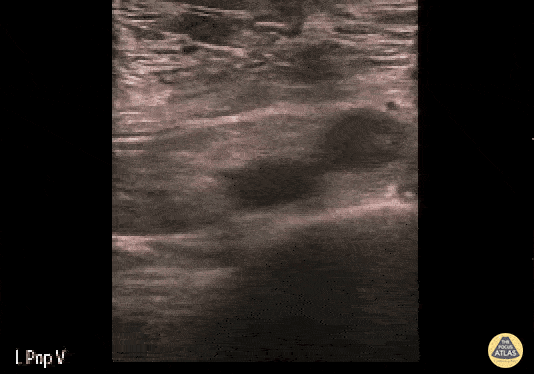

Vascular - Occlusive DVT of the Left Popliteal Vein

This clip demonstrates a non-compressible left popliteal vein consistent with deep venous thrombosis. Contributed by: Brittany Garza, DO; Saleem Nasseh, MD; Sadie Ellerson, MS4